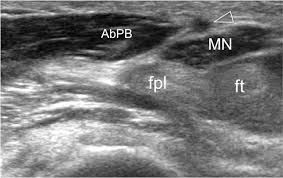

Deep cut on the palm side of the hand, wrist, or forearm can damage the tendons that bend the thumb. They have blood vessels and cells to maintain tendon health and repair injured tendon. Importantly, our case documents the appearance of fpl tendon hypoplasia on mri and ultrasound, which can help to distinguish between the two diagnoses. To differentiate from trigger thumb, patients with fpl rupture will have passive thumb flexion, but will not have active ip joint flexion. Palpate the flexor pollicis longus tendon as it crosses the proximal phalanx of the thumb on the palmar side. Repair of the damaged tendons is necessary to restore normal movement in the thumb and hand. While the fpl is not a separate muscle belly in extant great apes, a distinct tendon from the fdp belly might be present. But proximal muscles must stabilize the cmc and mp joints so that the glide of the fpl is directed distally to move the ip joint. As such, fpl tendon hypoplasia can be mistaken for fpl tendon rupture and vice versa. The fpl is the only tendon which is able to flex the interphalangeal joint of the thumb. Fpl.com is optimized for the following browsers and mobile operating systems: This muscle is located between the two muscles which facilitate flexion of the thumb, namely the flexor pollicis brevis and the abductor pollicis. The flexor pollicis longus muscles moves through the hand as a tendon.

Ie 9+, firefox 31+, chrome 37+, safari 6.1+, apple ios 7+ and android 4+. Fpl tendon hypoplasia and fpl tendon rupture can present similarly with isolated impairment of thumb flexion. The fpl tendon is the most commonly affected as it is the most radial tendon within the carpal tunnel. While the fpl is not a separate muscle belly in extant great apes, a distinct tendon from the fdp belly might be present. *if cleared by md and suture of adequate strength (four strand core repair with epitendinous suture augmentation). Flexor superficialis tendon transfers to the thumb: Conclusion fpl tendon rupture is a rare but serious complication of volar plate fixation performed for distal radius fractures. Palpate the flexor pollicis longus tendon as it crosses the proximal phalanx of the thumb on the palmar side. However, all tendons within the carpal tunnel can be affected. The fpl is the only tendon which is able to flex the interphalangeal joint of the thumb. As such, fpl tendon hypoplasia can be mistaken for fpl tendon rupture and vice versa. But proximal muscles must stabilize the cmc and mp joints so that the glide of the fpl is directed distally to move the ip joint. Tendons are fibrous cords, similar to a rope, and are made of collagen.